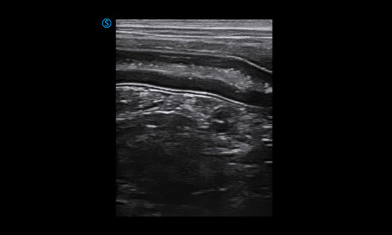

Digital Handheld Color Doppler Veterinary Ultrasound Imaging System

VP2 is SIUI's another innovative design of veterinary portable ultrasound system. Non-invasive, real-time and reliable diagnostic information for animal can be obtained within fast and easy manipulation.

VP2 provides various applications for veterinary diagnosis with micro convex probe and linear probe.

Heart

Kidney

Intestine